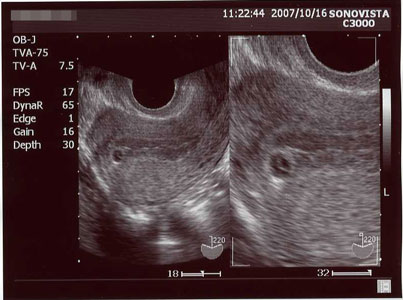

最終月経開始日は、2007年8月28日。

平日に仕事がお休み出来るのが、火曜日だけなため、10月9日(火)に産婦人科へ。

そこでの尿検査も「陽性」だったので、エコー撮影。

↓

折角撮ったのに、なーんにも写らなかった(;´・ω・)

まだ来院が早すぎたのかな?

でも陽性は陽性なので、また一週間後に再度検診です。

出産予定日も「?」マークw